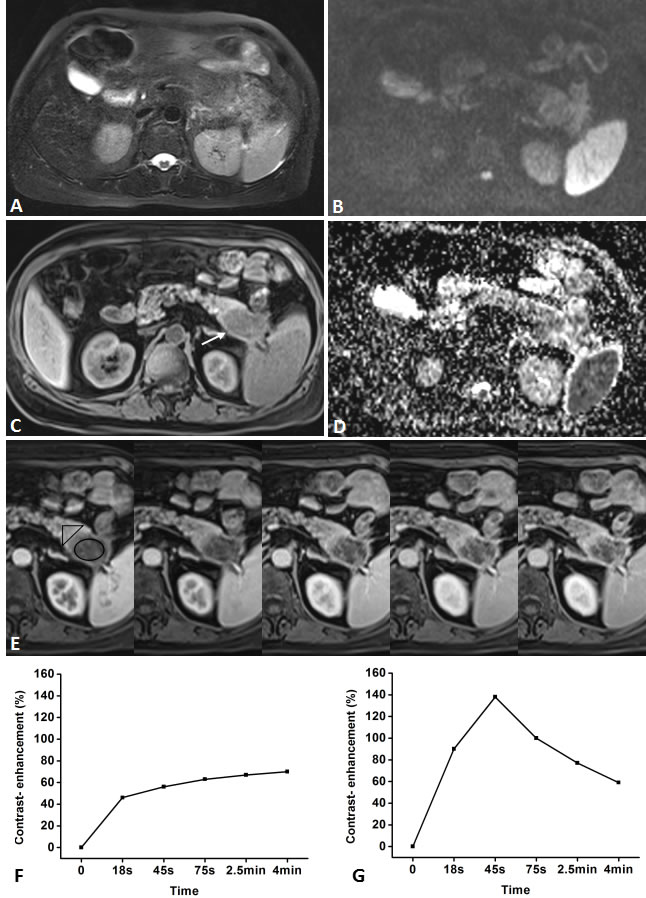

Figure 3: Representative pancreatic T2-weighted image (A), DWI with a b value of 600 s/mm2 (B), T1-weighted image (C), ADC map (D), DCE-MR images (E), and TIC profiles (F, G) in a 62-year-old man with pancreatic carcinoma in the tail of pancreas (white arrow). DCE-MR images: 18s, 45s, 75s, 2.5 and 4min aftercontrast injection with constant gray scale. The ROIs of mass and non-mass adjacent parenchyma (NAP) indicated with black circle and black triangle. Pancreatic mass demonstrates type-VTIC which shows a slow, gradually increasing enhancement pattern, while NAP demonstrates type-II aTIC which shows a rapidly increasing then gradually decreasing enhancement pattern. DWI shows pancreatic mass is clearly seen as isointense withmoderately-defined margin.